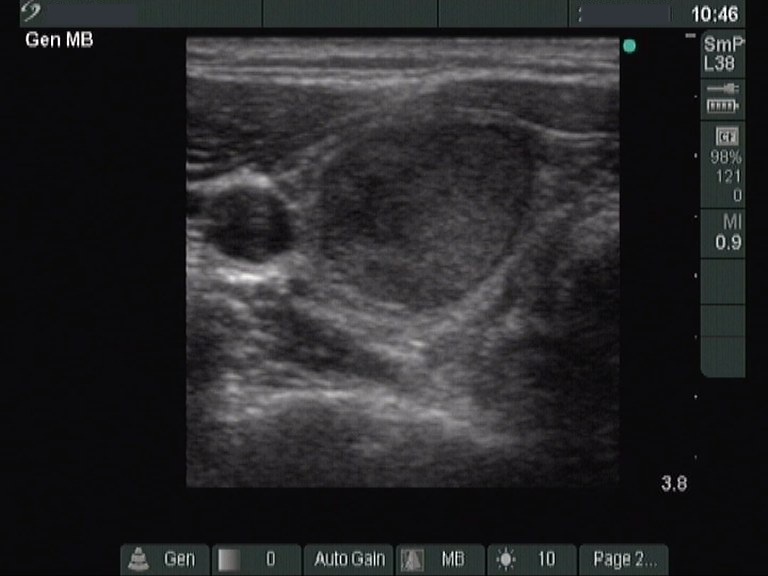

Ultrasonography: revealed hypoechogenic inhomogeneous thyroids. There was a moderately hyperechogenic nodule in the left lobe. The nodule presented a halo sign and perinodular blood flow.